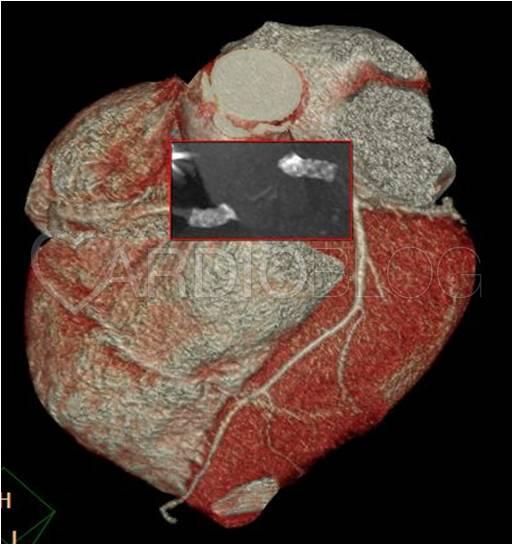

<p><strong><em>4.Kép:</em></strong><em> 3D rekonstrukció, szájadékokban stentek ábrázolódnak.</em></p>